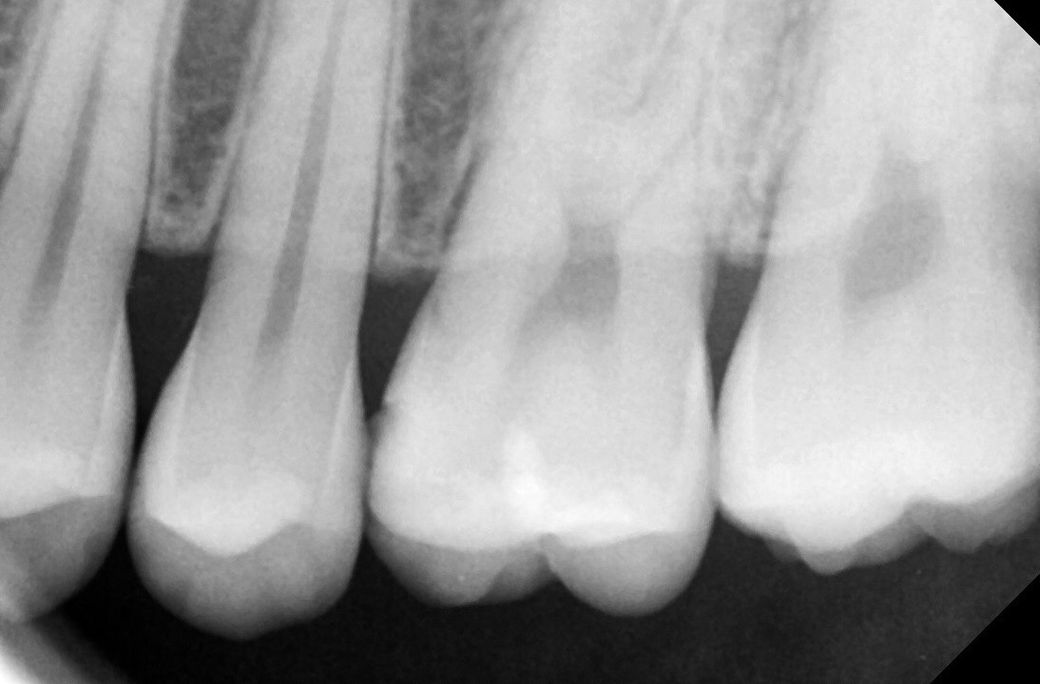

3치과 엑스레이 찍고 확인이 어려워 근접 엑스레이

추가 촬영 했지만 너무 작거나 안보인다

• 2번 째 사진

본인기준 오른쪽 위 작은어금니 충치 큰 엑스레이 사진상에서 보이네요 치료해야할 정도입니다

작은 엑스레이 사진은 왼쪽 작은어금니 찍은겁니다